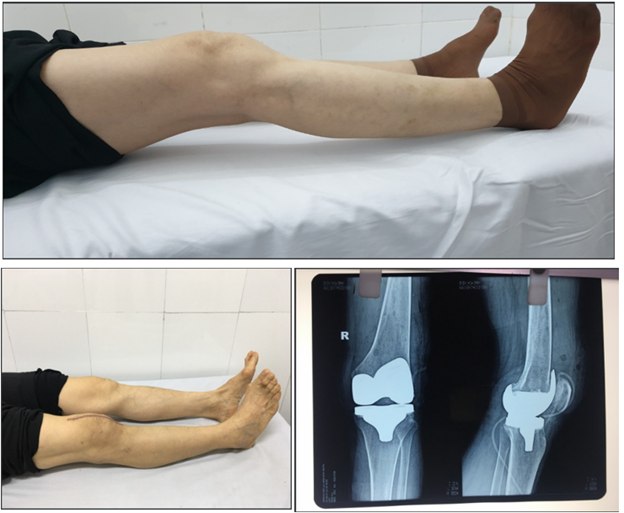

Phẫu thuật

• Mổ thay khớp

Phương pháp phẫu thuật chỉ được dùng khi những cách điều trị khác không có hiệu quả và đây là cách không khuyến khích áp dụng vì có nhiều rủi ro.